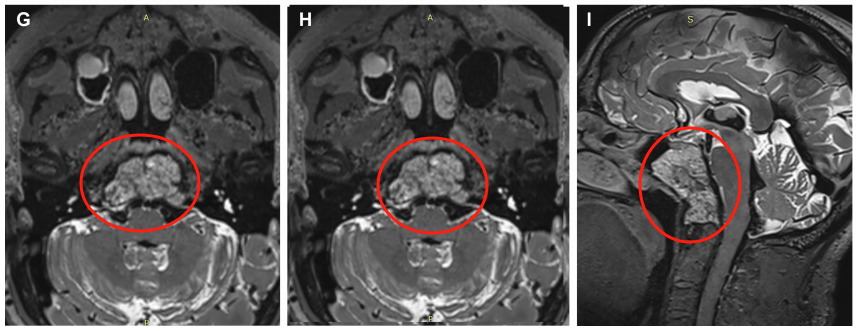

▼术前MRI显示一个大的斜坡脊索瘤延伸到蝶窦,寰枢椎、岩尖、下斜坡和右枕髁。

▼术后MRI证实肿瘤完全切除,显示用于术后残腔重建填充的脂肪(白色箭头表示脂肪移植)。